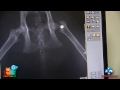

Złamanie kości szyjki udowej u kota